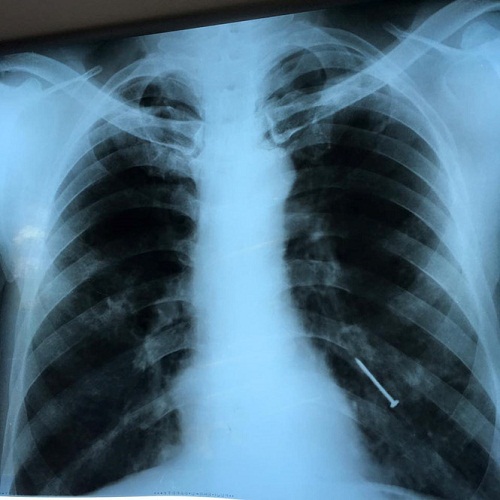

Sau 4 tháng, bệnh nhân ho liên tục có khi ho ra máu nên tìm đến Bệnh viện tuyến tỉnh khám, sau khi chụp CT phát hiện có dị vật trong phổi đã được chuyển lên tuyến trên.

Dị vật là cây đinh dài khoảng 6cm đã gỉ sắt. Ảnh: Báo Thanh niên |

Bác sĩ Phạm Thị Vân Thanh, Khoa Nội soi, BV Chợ Rẫy, TP.HCM chia sẻ với báo VTC News cho biết, ekip điều trị đã tiến hành nội soi bằng ống mềm, gắp thành công dị vật là cây đinh đã gỉ dài khoảng 6cm khỏi phế quản của bệnh nhân. Sau khi lấy dị vật, tình trạng ho ra máu của bệnh nhân được khắc phục, chỉ còn viêm phổi nhẹ, dự kiến sẽ nhanh chóng tự hết.